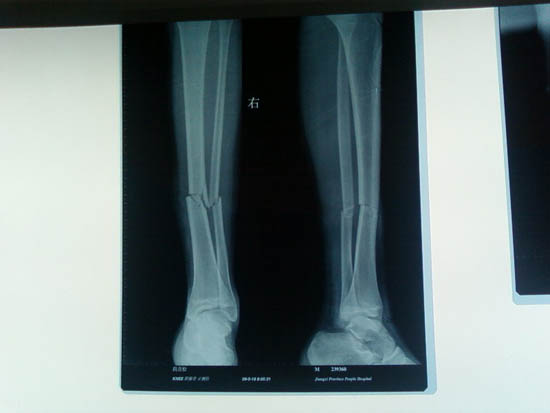

胫骨骨折微创切口钢板内固定图例

张同学是一位16岁的高中生,一次摔伤导致他下肢骨折,家属立即带着他到江西省人民医院就诊。因为孩子正在上学,处于生长发育期,小张及家长精神都较紧张,对治疗不了解,孩子心理压力大害怕治疗,尤其害怕手术治疗,他们一家人对选择非手术还是手术治疗举棋不定。

小张入院后骨二科与病人及家属多次沟通,告知如采取夹板、石膏固定非手术治疗,骨折复位不可能很好,且病人患肢活动受限膝关节、踝关节易僵硬;治疗时间长影响病人学习。而运用小切口复位钢板固定,手术创伤小、术后疤痕小,病人可早期活动,对关节功能恢复好。小张及家属经考虑后选择了微创手术钢板内固定治疗,术后小张恢复的很快,并且没耽搁学习。